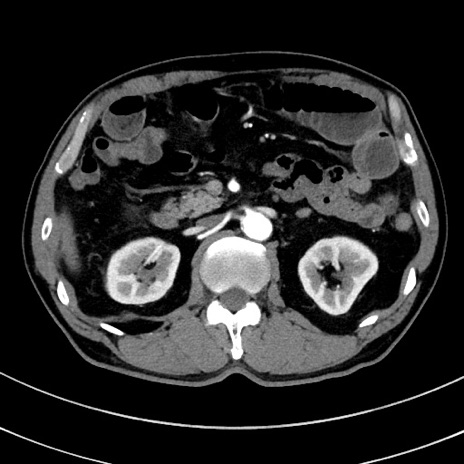

症例8(横断像)

【症例】 60歳代男性

【主訴】 黒色吐物

【現病歴】 4日前から嘔気自覚、2日前の朝食後にも嘔気あり、自分で手で嘔吐反射起こし嘔吐したところ血が混ざっていたため受診。

【既往歴】 5年前汎発性腹膜炎を伴う急性虫垂炎で手術、高血圧、前立腺肥大症、高脂血症

【身体所見】 腹部正中に手術癩痕あり 腹部平坦・軟圧痛なし膨満感あり

【データ】WBC 8400、CRP 4.54